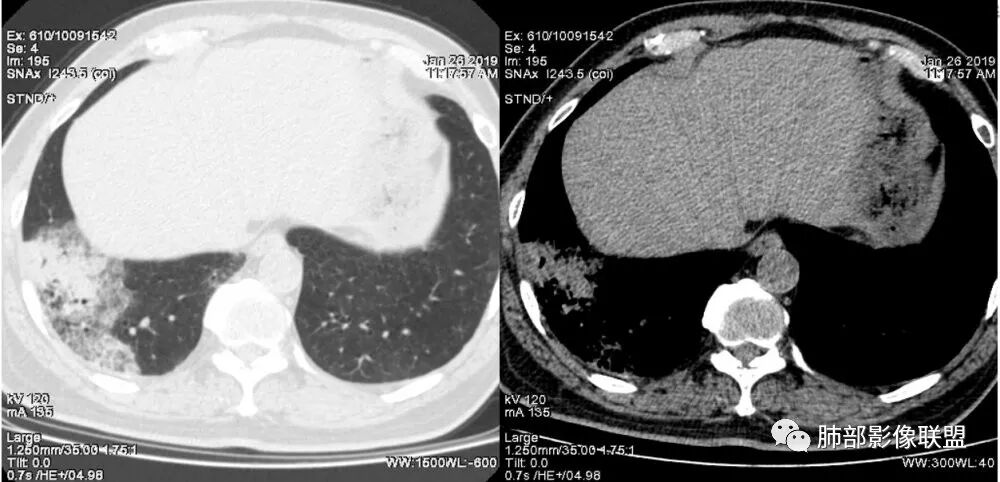

老年女性,右肺下叶沿胸膜下大片状高密度影,外周磨玻璃影,边界较清,内可见蜂窝征及支气管充气征,考虑肺炎型肺癌。

老年女性,咳嗽咳痰病史,右肺下叶大片磨玻璃实变影,胸膜下分布,支气管进入后扩张、僵直,磨玻璃影边界清楚,考虑粘液腺癌。鉴别肺炎。

右肺下叶基底段靠胸膜实变/磨玻璃混杂密度影,边界清楚,内见多发空泡(蜂窝样趋势改变?); 临床:咳嗽咳痰,无发热、胸痛; 考虑腺癌:无发热,感染性病变不首先考虑;部分层面形态类楔形,鉴别肺栓塞

老年女性,右下肺实变影,病灶里有小叶内间质增厚,周围GGo,支气管扩张,粘液性腺癌?淋巴瘤?

中年女性,咳嗽咳痰。右肺下叶片状高密度影,部分实性密度,周围见边界清晰磨玻璃影,内见小空泡,实性区部分支气管堵塞,有重力效应,考虑肺炎型肺癌,建议查痰脱落细胞。

老年人,右肺下叶斑片状阴影,病灶有膨胀性,边缘可见磨玻璃影,其边界清晰,内见僵硬的支气管,部分支气管扩张,首先考虑占位性病变,粘液性腺癌可能。鉴别感染性病变,后者边缘多有收缩性改变或者平直,内部支气管走形自然。

1.本例病灶较大片混杂密度影,胸膜下分布为主(未沿着支气管分布),该分布特点可见于大叶性肺炎、干酪性肺炎、淋巴瘤及粘液腺癌等。可惜未提供增强扫描图像。

2.病灶示中央实变区,周围GGO,可见明显小叶间隔增厚,GGO边界清楚,应当考虑到恶性病变的可能性。肺炎因炎性水肿及渗出,影像上边界常模糊不清,注意早期粘液腺癌可出现似清非清的边界。粘液腺癌因粘液成份较多,密度一般偏低,纵隔窗病灶常会消隐或范围会明显缩小,这不同于炎性实变。

3.病灶内支气管走形略显僵直,侧支少(粘液阻塞),也符合肺腺癌的枯树枝征。而大叶性肺炎的支气管是管壁光整、通畅、自然,结核的支气管常常壁增厚,甚至狭窄后扩张;